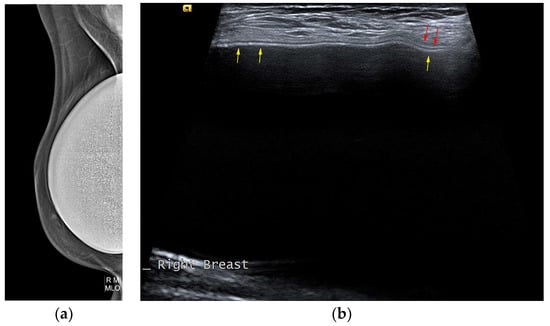

5.2.5. Implant Rupture

- Seiler, S.J.; Sharma, P.B.; Hayes, J.C.; Ganti, R.; Mootz, A.R.; Eads, E.D.; Teotia, S.S.; Evans, W.P. Multimodality Imaging-based Evaluation of Single-Lumen Silicone Breast Implants for Rupture. Radiographics 2017, 37, 366–382. [Google Scholar] [CrossRef] [PubMed]

- Ahn, C.Y.; DeBruhl, N.D.; Gorczyca, D.P.; Shaw, W.W.; Bassett, L.W. Comparative silicone breast implant evaluation using mammography, sonography, and magnetic resonance imaging: Experience with 59 implants. Plast. Reconstr. Surg. 1994, 94, 620–627. [Google Scholar] [CrossRef] [PubMed]

- Ikeda, D.M.; Borofsky, H.B.; Herfkens, R.J.; Sawyer-Glover, A.M.; Birdwell, R.L.; Glover, G.H. Silicone breast implant rupture: Pitfalls of magnetic resonance imaging and relative efficacies of magnetic resonance, mammography, and ultrasound. Plast. Reconstr. Surg. 1999, 104, 2054–2062. [Google Scholar] [CrossRef] [PubMed]

- O’Toole, M.; Caskey, C.I. Imaging spectrum of breast implant complications: Mammography, ultrasound, and magnetic resonance imaging. Semin. Ultrasound CT MRI 2000, 21, 351–361. [Google Scholar] [CrossRef] [PubMed]

- Salzman, M.J. Silent Rupture of Silicone Gel Breast Implants: High-Resolution Ultrasound Scans and Surveys of 584 Women. Plast. Reconstr. Surg. 2022, 149, 7–14. [Google Scholar] [CrossRef]

- Goldammer, F.; Pinsolle, V.; Dissaux, C.; Pelissier, P. Accuracy of mammography, sonography and magnetic resonance imaging for detecting silicone breast implant ruptures: A retrospective observational study of 367 cases. Ann. Chir. Plast. Esthet. 2021, 66, 25–41. [Google Scholar] [CrossRef]

- Rochira, D.; Cavalcanti, P.; Ottaviani, A.; Tambasco, D. Longitudinal Ultrasound Study of Breast Implant Rupture Over a Six-Year Interval. Ann. Plast. Surg. 2016, 76, 150–154. [Google Scholar] [CrossRef]